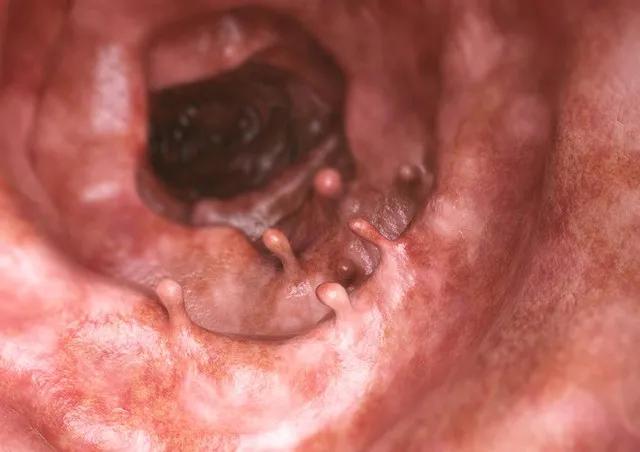

肠息肉切除后又长出来,这是许多患者面临的困扰。一项对近万名大肠息肉患者的调查显示,大约50%的患者在术后4年内出现了息肉复发。为什么会出现这种情况?中医对此有何独到见解?

肠息肉复发的原因主要有三:一是未完全切除,二是环境因素未改变,三是遗传因素。如果息肉较大或位置特殊,可能难以完全切除,残留的组织会继续生长。即使完全切除了息肉,如果导致息肉形成的环境因素(如饮食习惯、生活方式等)没有改变,息肉仍有可能再次出现。此外,遗传因素也是导致息肉复发的重要原因。